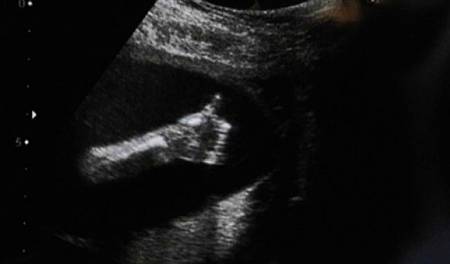

Nu mereu reușești să surprinzi atât de bine anumite imagini de ecograf. Tocmai de aceea, imaginile prezentate sunt foarte RARE!

De-a lungul timpului au fost surprinse mai multe imagini de ecograf cu adevărat uluitoare!

Iată mai jos 10 imagini de ecograf unice!